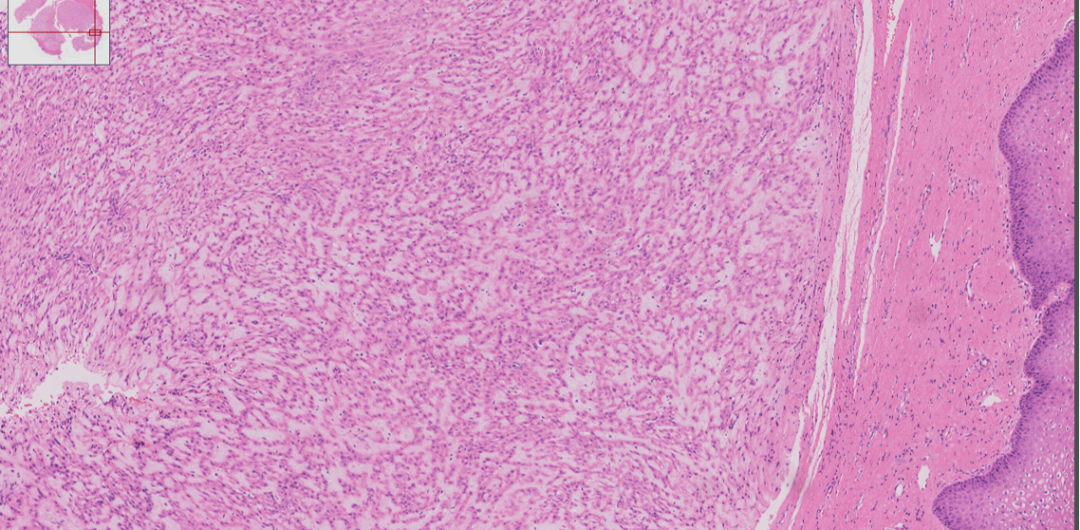

中倍镜下肿瘤结构呈丛状,条索状生长,间质黏液变性

肿瘤呈丛状,条索状生长,间质黏液变性

细胞温和,圆形、多边形,胞浆丰富,嗜酸性,可见核仁

偶见核分裂